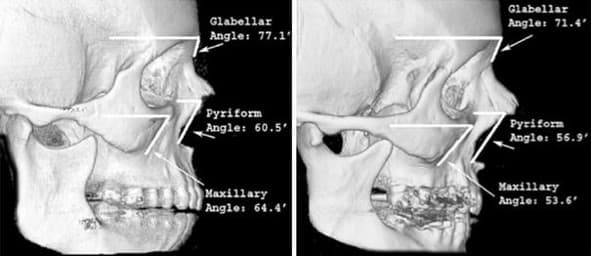

楊仕安醫師進一步補充,事實上下巴本來就是人體最早開始老化的骨骼部位之一。從35歲後,包括頦骨、齒槽骨和下顎角都可能因荷爾蒙下降、鈣質攝取不足、抽菸或遺傳影響而出現骨質退化的狀況。

另有文獻證實,先天骨骼支撐較差的人,老化的視覺表徵往往會更加明顯,例如輪廓鬆垮、下臉比例失衡、甚至嘴凸感加劇等問題,都讓人看起來更顯老態。若能在評估結構後,透過合適的醫療協助補強下巴支撐,不僅有助於改善輪廓線條,更有其恢復美觀與年輕感的實質意義。

▲左側年輕組與右側年老組的對比顯示骨質隨著老化流失